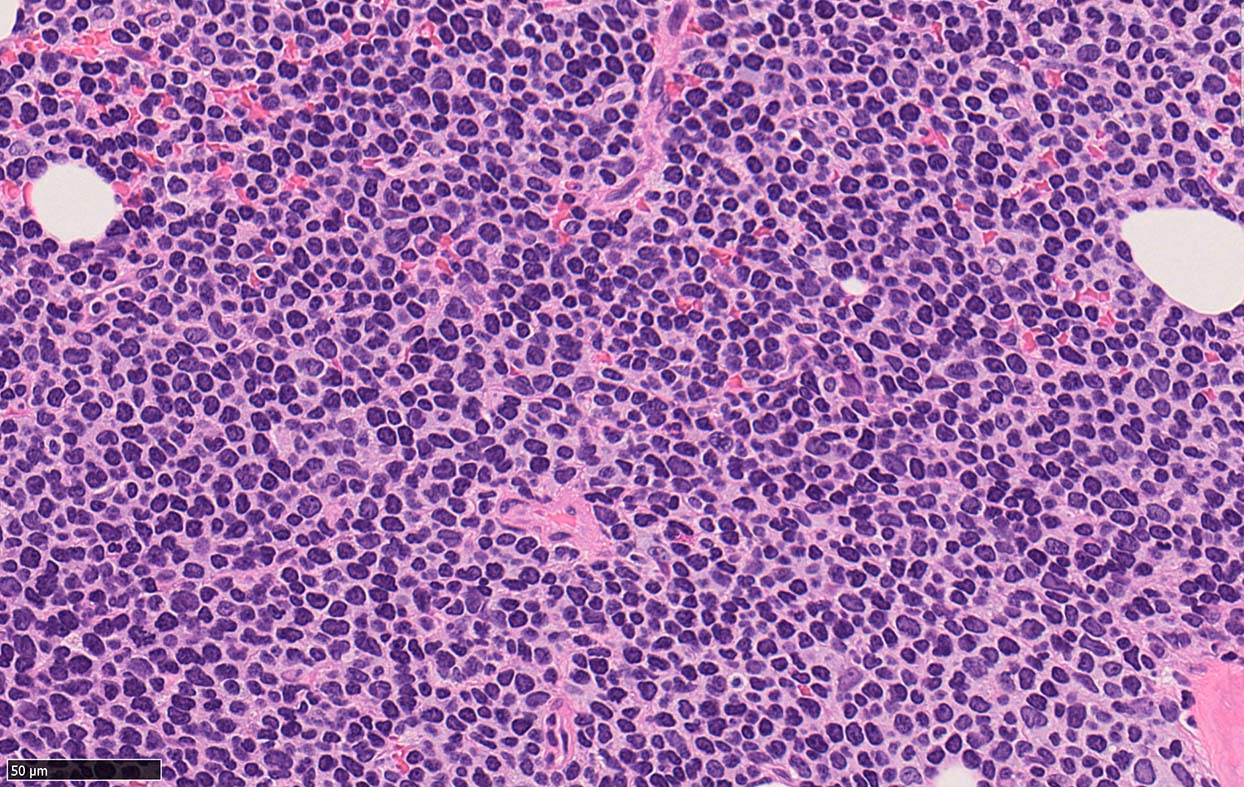

Bone marrow involvement of mantle cell lymphomaの症例

骨髄骨梁間に密なASD-Giemsa陰性の小型~中型円形細胞の浸潤が認められる.

MCLは60-90%の症例で骨髄に浸潤する. *1*2*3*4*5. 骨髄浸潤の最も一般的なパターンは, focal random(限局性, ランダム)で, 80%以上の症例でみられる.

骨梁間(interstitial)には約50%, びまん性浸潤は20~30%の症例でみられる。*1,*6 とくに, 傍骨梁浸潤は45%の症例に認められる. 時には、濾胞性リンパ腫に似た傍骨梁のみの浸潤を認めることもある. まれに、顕著な類同内浸潤を伴う症例も報告されている。*7